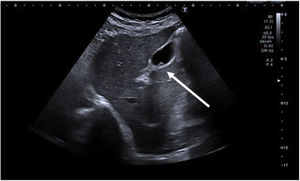

| Adenomyomatosis | Proliferation of epithelium with hypertrophy of the muscular layer with invaginations of hypertrophic mucosa through the thickened muscular layer (Rokitansky-Aschoff sinusoids); may be diffuse, segmental or focal. | Wall thickening with cystic spaces and comet-tail artifact (hyperechoic focus with posterior acoustic reverberation in the shape of an inverted triangle, with gradual decrease in echogenicity [Fig. 2]) |